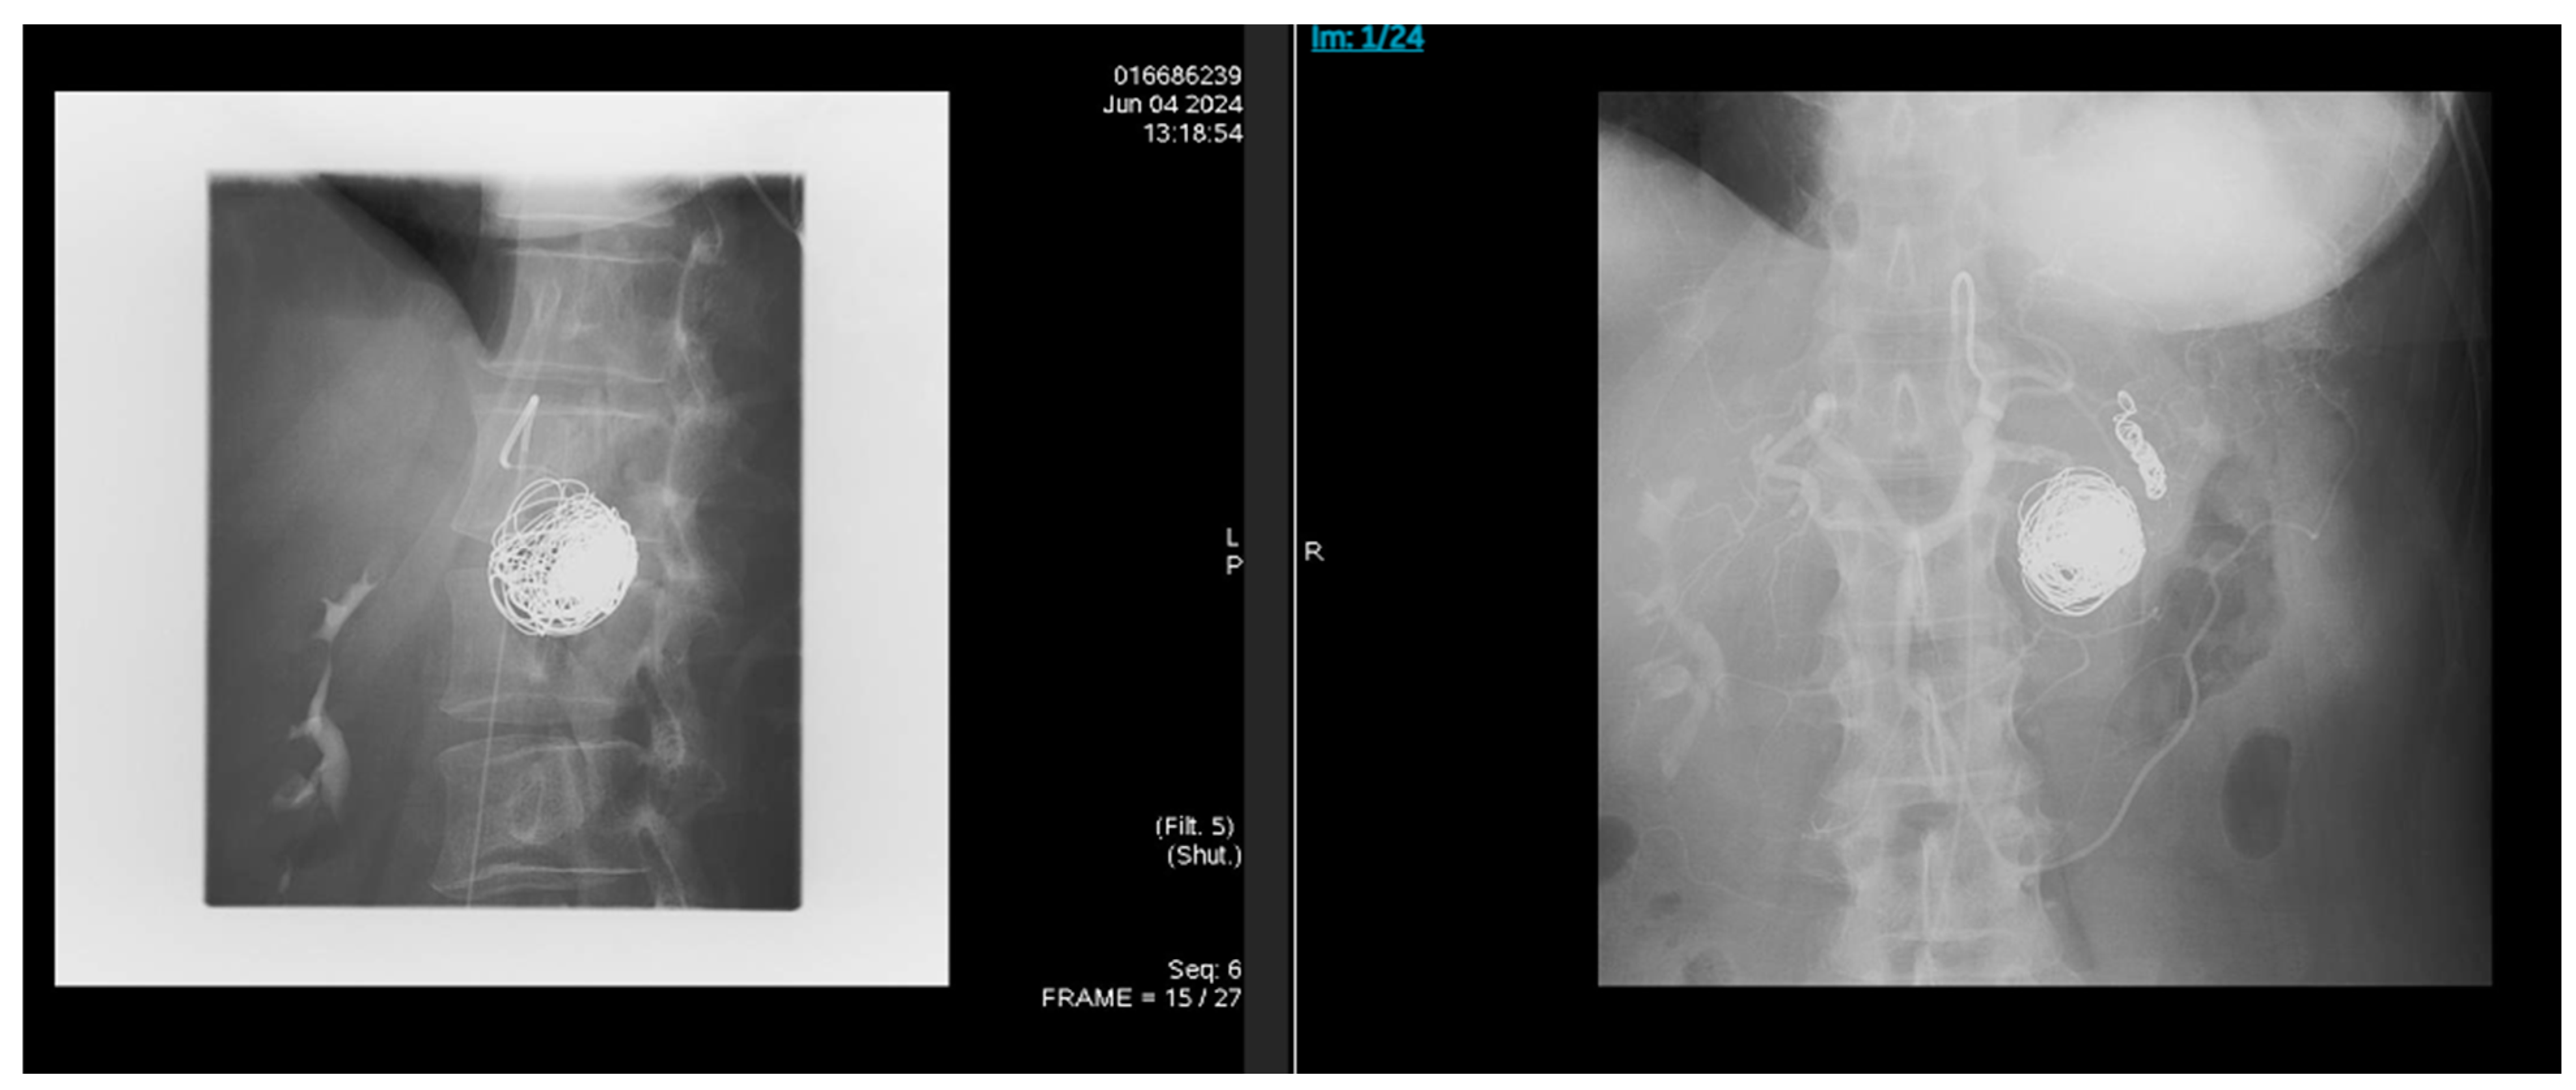

Fatal Recurrent Splenic Artery Pseudoaneurysm Rupture Despite Prior Successful Embolization in Alcohol-Associated Chronic Pancreatitis: A Case Report

2. Case Presentation